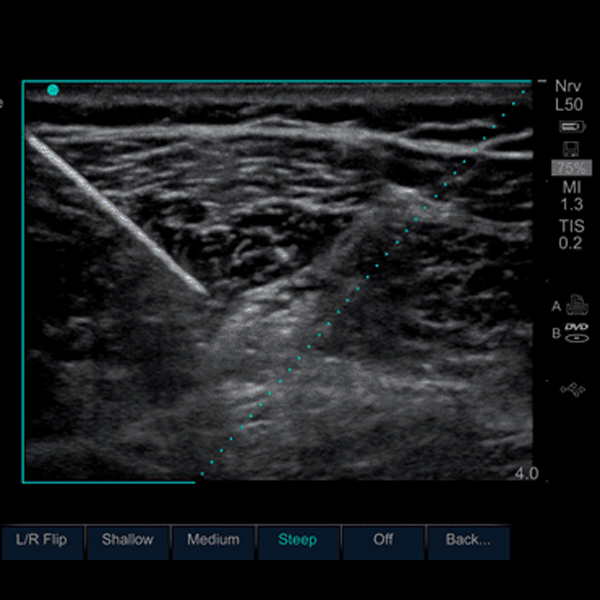

Ultrasound is a valuable tool for guiding medical procedures, such as biopsies, injections, and drainages. However, it can be difficult to visualize a needle in ultrasound images, especially when the needle is small or moving quickly. This can lead to complications during the procedure, such as accidental tissue damage or needle misplacement. Needle visualization (NV) is a technique that improves the visibility of needles in ultrasound images. It works by using a combination of software and hardware to enhance the needle's echogenicity. This makes the needle easier to see, even in challenging situations.

Needle Visualization is a relatively new technique, but it has quickly become an essential tool for ultrasound-guided procedures.